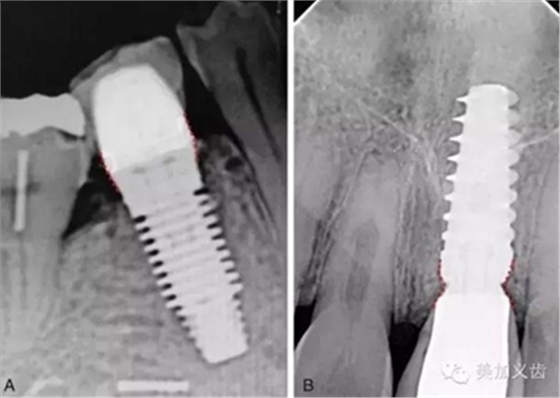

但根尖片是種植中必不可少的檢查,可以用來檢查基臺與種植體、修復體與基臺之間的密合程度,或者用于術后隨訪。

值得注意的是:使用根尖片來進行術后隨訪,這是種植術后很重要的一件事情,而且需要定期來做,然后將拍攝出來的根尖片進行對比,才能看到是否有骨吸收。但如果你每次拍攝的角度都不一樣,結(jié)果會讓你嚇一跳,怎么某段時間內(nèi)骨吸收這么多?!怎么某段時間骨頭又長上來了?!太令人費解了!

其實是你拍攝的角度不一樣,所得到的結(jié)果也不一樣,因此,采用平行透照技術就十分關鍵,否則你的術后回訪是沒有意義的。平行透照技術很簡單,通過X線片定位器就可以做到,讓你的X線接收器和管球平行,這樣每次拍攝的角度都是一樣的了。